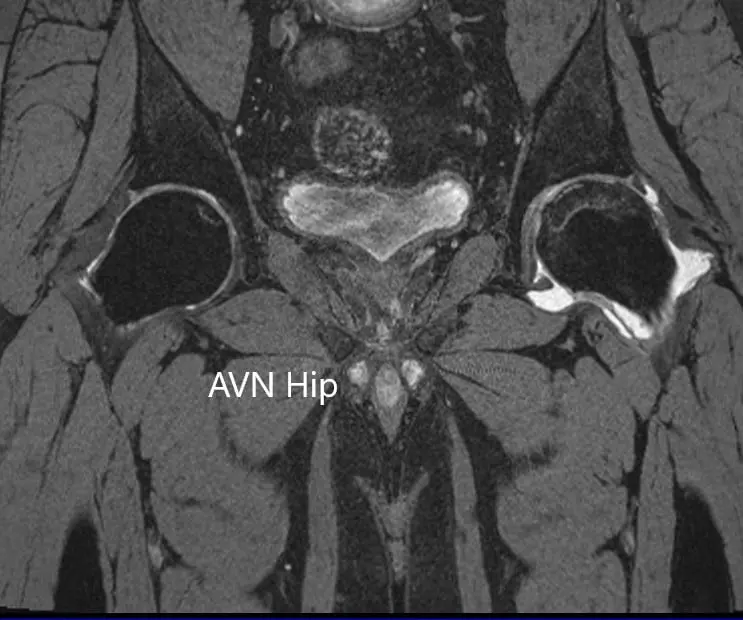

Imaging studies obtained in the form of an X-Ray suggested sclerosis of the left head of the femur. There were marked acetabulum changes. An MRI was further obtained suggesting avascular necrosis of the superior lateral head of the femur with changes in the acetabulum. There was marked hypointense areas on both T1WI and T2WIs.

T1WI coronal section of MRI showing AVN hip

T1WI coronal section of MRI showing AVN hip.